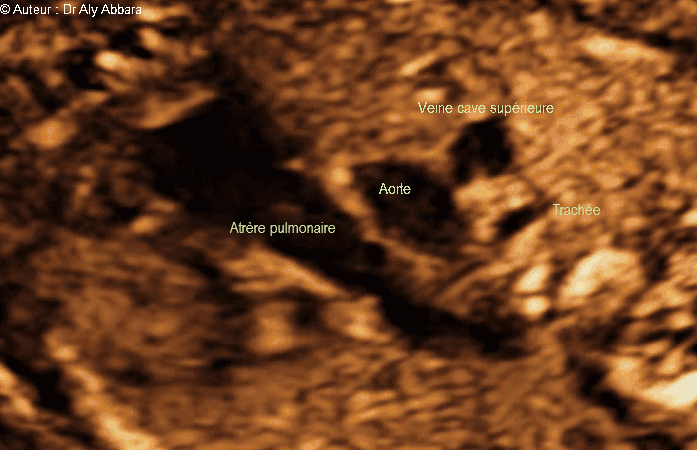

Images échographiques montrant l'aspect normal de la coupe cardiaque " Trois vaisseaux et trachée " qui comporte de haut en bas sur cette image :

* La veine cave supérieure juxtaposant la portion terminale de la trachée.

* L'aorte (coupe passant par sa crosse).

* L'artère pulmonaire se prolongeant par le canal artériel qui se jette dans la crosse de l'aorte.

Foetus de 22 SA et 3 jours.